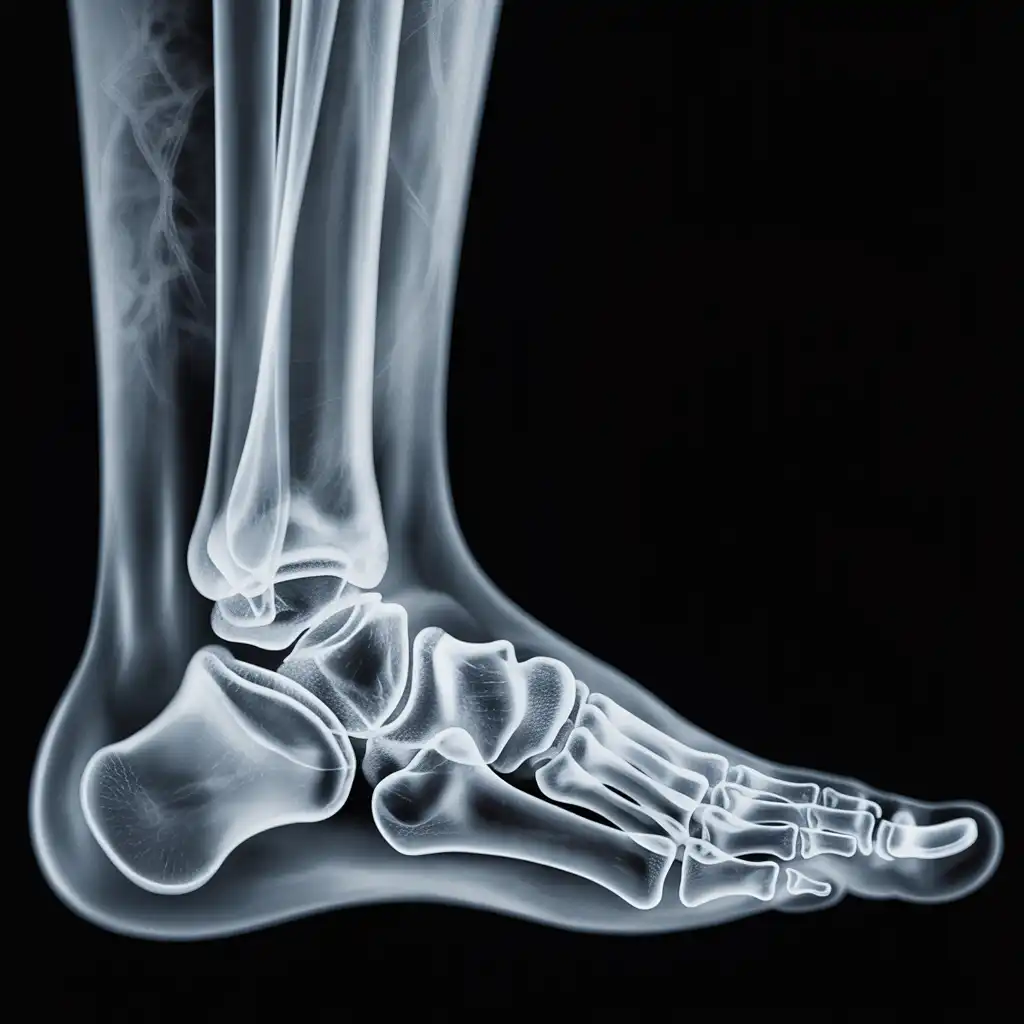

Il professionista entra con apparecchiature a basso dosaggio e schermi protettivi: bastano 2 × 2 m di spazio vicino al letto o alla poltrona. In pochi minuti acquisisce immagini HD, proprio come in un reparto ospedaliero.

Il medico radiologo analizza le immagini e firma il referto digitale all’istante. Ricevi il referto cartaceo e le immagini su chiavetta USB consegnati direttamente a casa tua subito dopo l'esame.

Usiamo le stesse apparecchiature certificate CE dei reparti ospedalieri, calibrate regolarmente. I referti sono validi per visite specialistiche, pronto soccorso e pratiche assicurative, e restano archiviati per 10 anni per ogni esigenza futura.